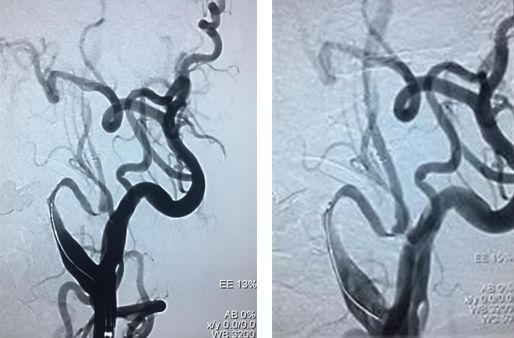

造影右侧椎动脉闭塞,右侧颈总动脉

左侧颈总、左侧椎动脉

左锥造影V4段先天性病变(狭窄?)

右椎入路微导管手推造影,寻找血管闭塞位置

右椎V4段狭窄,2.5*15球囊扩张(应用替罗非班)